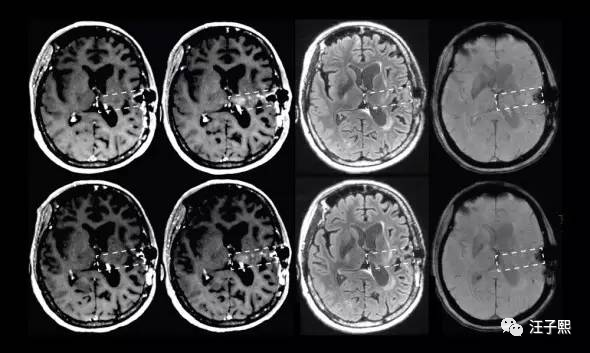

Jerry之前的文章 记一次SAP开发工程师给微软Azure报incident的体验,也提到自己处理incident和给别的程序员报incident的经历,没想到,这次有医生给我身上这台生物系统报了incident,而且priority还是very high的。一个专业的程序员,在接到incident之后,都是从“问题重现-问题定位-设计解决方案-处理问题-测试”这几个步骤进行的。我最近,凭着Google和金山词霸,也在看相关的英文论文,从病的诱因,诊断,治疗和预后这几个方面来学习,恶补了一大堆理论知识,虽然对我实际可能没什么用,甚至会让我的情绪变得消极,然而我的这些行为都是一个程序员的职业习惯使然——不管遇到什么问题都想刨根究底。